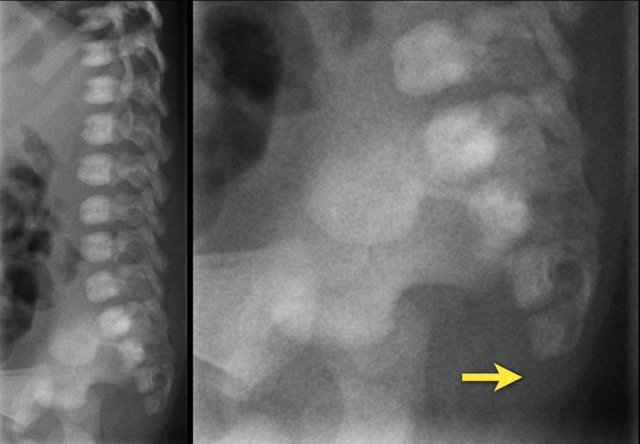

The plain film shows a fusion of S4 and S5.

This was a newborn boy with an anorectal malformation.

An ultrasound was performed to look for signs of occult spinal dysraphism.

There is a thickened filum with a low ending conus medullaris at L3-L4 and a mild hydromyelia.

Continue with the sagittal video.

On the sagittal video the low ending conus medullaris is seen at L3-L4.

The upper limit of normal for the width of the filum terminale is 2 mm.

If it is thickened it often shows fatty infiltration with hyperechoic tissue.

In healthy newborns, the tip of the conus medullaris is located between L1 and L2.

The tip should not be positioned below L2-3.

This image is of a newborn girl with an anorectal malformation.

The distal sacrum below S4 is absent (arrow).

Since an anorectal malformation is frequently associated with spinal pathology, an ultrasound was performed.

If a plain film of the vertebral column demonstrates an anomaly of the sacrum, there is a 50% change of an intraspinal anomaly.

In most cases there is a low ending tethered cord.

In some cases however the cord ends at the normal position, but is deformed.

This is a so-called blunt cord terminus.

There is generally a wedge-shaped ending in which the dorsal side reaches further caudally than the ventral side.

Ultrasound of the spine shows a blunt cord terminus at T12-L1.

A blunt cord terminus is a sign of caudal regression syndrome characterized by abnormal development of the lower end of the spine.

On ultrasound the absent coccyx is also visible.